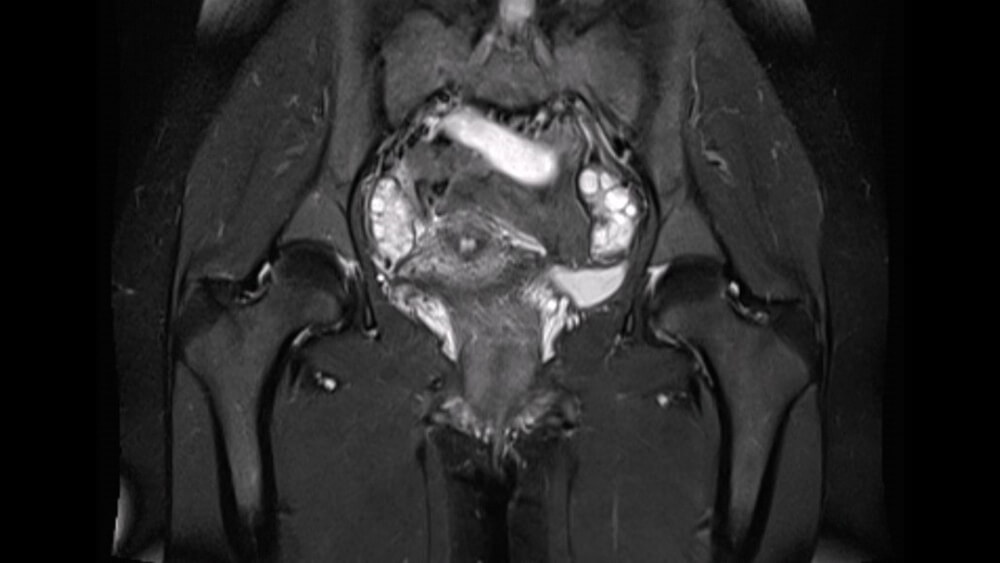

Uterine Film is the shots that help in imaging the uterine cavity in order to diagnose obstruction, stenosis, width or other problems of the uterine tubes. The uterine tubes may become blocked due to various reasons or may bring other problems.

It helps to have more information about the uterus and uterine tubes when performing imaging procedures of the lower abdomen. If the tubes that help the egg and sperm meet are open, it allows the baby to complete 9 months in the womb. If the tubes are closed or narrow, the pregnancy realization rate is quite low. That is why, together with the uterine film that will be made, it helps to have more information about this topic.

For the imaging process, a concentrated substance is used to provide an image to the device. It allows the intrauterine and uterine tubes to become more visible with the fluid to be given from the cervix. It is not possible for the liquid being used to harm the person or for any complications to occur later.

Because there is iodine salt in the liquid. Thanks to this iodine, it takes on the task of keeping X-rays in an eclipsable state. Since the liquid has no smell, it is not possible for a situation to occur that will disturb the person. It is not caustic and is colorless. The liquid has no such condition as damage to organs or tissues. In this way, an image is taken from inside the uterus with uterine tubes.

It ensures that menstrual irregularity, infertility, continuous miscarriage events, myoma, tube condition and many conditions related to the uterus can be detected. In order to obtain better quality images before the procedure, fluid is injected into the uterus. In this way, the HSG film is used to remove the adhesion that occurs in the uterus.